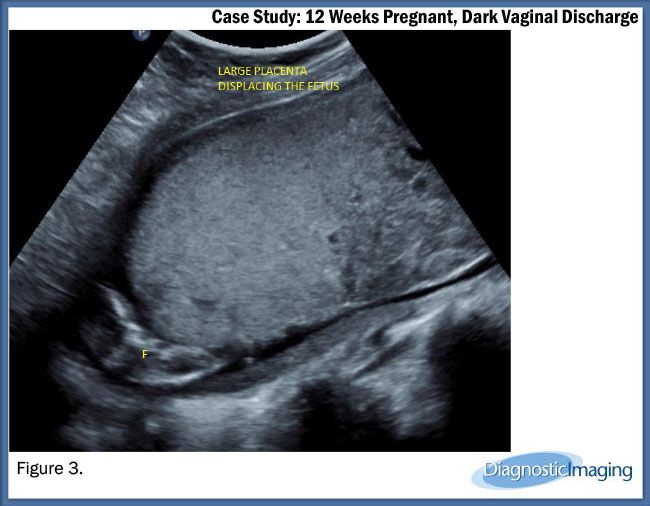

Case History: 28-year-old, G1P0, 12 weeks gestation with dark vaginal discharge.